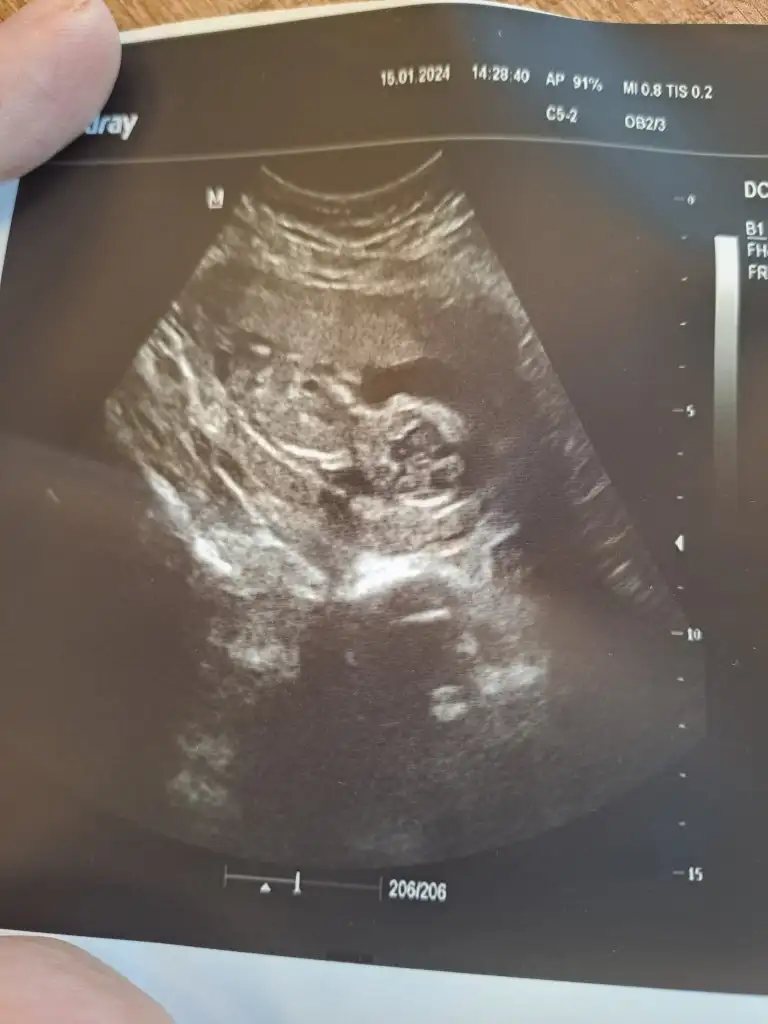

Merhaba benim içinde bir tahminde bulunur musunuz doktorum bir tahminde bulunup değişirse şaşırırım ama 16 da netleştiririz dedi acaba aynı fikirde misiniz![]()

KızMerhaba, burda 13+3 günlüğüz, sizce cinsiyeti ne olabilir